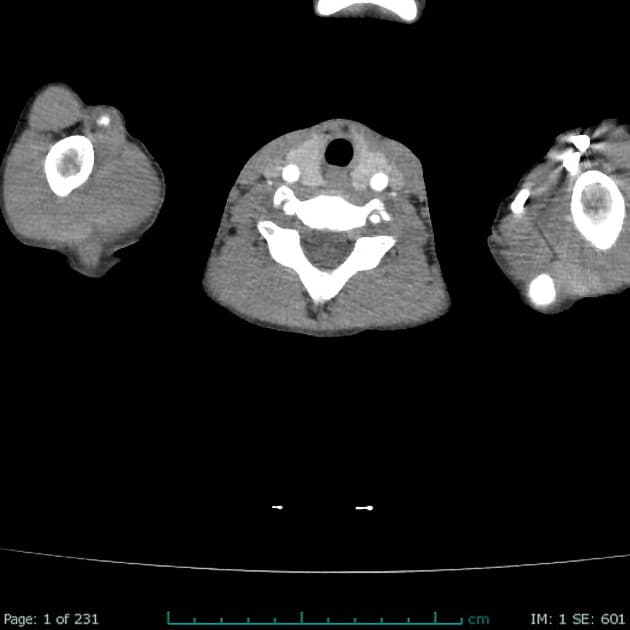

Axial with rectal contrast C+ portal venous phase

Hình ảnh ghi nhận tình trạng hạch mạc treo bụng và vùng sau phúc mạc hoại tử kèm theo các tổn thương giảm tăng quang ở lách.

Dịch ổ bụng (ascites) mức độ nhẹ và tràn dịch màng phổi (pleural effusion) trái mức độ nhẹ.

Ghi nhận một hạch hoại tử liên quan mật thiết với đoạn đại tràng xuống gần nhất.

Xét theo độ tuổi và tiền sử bệnh nhân, hình ảnh này có thể đại diện cho lao lách (splenic tuberculosis) kèm viêm hạch (lymphadenitis).